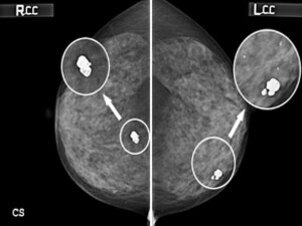

유방의 좌우 측면을 보여주는 유방촬영술(맘모그램) 이미지로, 양쪽에 둥글게 표시된 부분과 화살표로 강조된 석회화 병변이 보인다.

유방촬영술에서 발견된 석회화 병변

미세석회화는 대부분 유방촬영술(맘모그램)을 통해 발견됩니다. 수진이 겪었던 진단 과정을 따라가며, 유방 미세석회화 발견과 진단 과정에 대해 알아보겠습니다.